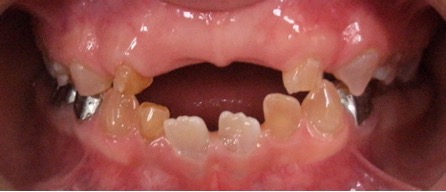

El examen clínico intraoral reveló alteración de la estructura y color de las piezas primarias, atrición y pérdida de la dimensión vertical (Figura 2). Radiográficamente se observó la presencia de coronas con marcada constricción cervical y raíces cortas (Figura 3). Presentaba alto riesgo cariogénico, por la presencia de lesiones de caries activas y dos restos radiculares, sumado a la anomalía estructural de la dentina (riesgo biológico específico) y bajo riesgo gingivoperiodontal. El riesgo socio-económico era alto por provenir de una familia con marcadas limitaciones económicas. Luego de la anamnesis, examen clínico y radiográfico, e interconsulta con el médico de cabecera se estableció el diagnóstico de DI Tipo I asociado a OI tipo I. Se planificó un tratamiento integral y preventivo con los objetivos de devolver forma y función, y proteger y evitar el desgaste de los tejidos conductas que pudieran interferir con el tratamiento.

Figura 2: Examen clínico intraoral del maxilar superior e inferior y vista anterior. Año 2007

Según la literatura si bien la DI tipo I involucra ambas denticiones, la dentición primaria se ve más seriamente comprometida2,4,9 situación que también se presentó en nuestro paciente. Debido a la gran pérdida de estructura dentaria y atrición de la dentición primaria, se optó por la colocación de coronas de acero en los molares primarios. Los superiores además formaron parte del mantenedor de espacio fijo para reponer las piezas 51 y 61. Las coronas de acero resultaron una medida eficaz que además de proteger a la estructura dentaria, compensaron la dimensión vertical disminuída.2, 3

Cuando la dentición permanente está implicada, los incisivos inferiores son los más comprometidos, presentando en estos casos una coloración intensa propia de la DI (O’Connell, Marini 1999, Majorana, Bardellini et al. 2010, Petersen, Wetzel 1998), como se observa en el paciente. Las piezas permanentes fueron monitoreadas desde su erupción, recibieron protocolos preventivos con barnices fluorados, pastas y enjuagatorios fluorados domiciliarios, conjuntamente con un adecuado control de higiene oral.15